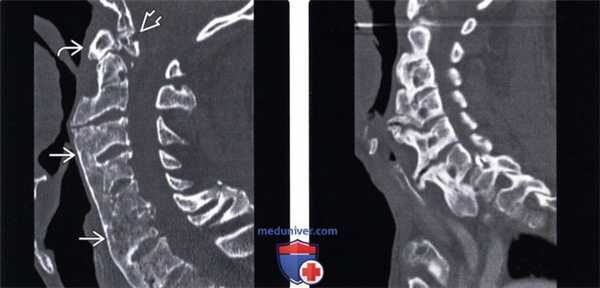

(Слева) КТ, сагиттальный срез: сливающиеся вентральные спондилофиты, распространяющиеся от уровня С2 до верхнегрудного отдела позвоночника. Костный блок на уровне С2-СЗ отсутствует, обеспечивая некоторую подвижность данного сегмента. Обратите внимание на «затупленный» зубовидный отросток, гипертрофию передней дуги С1 и зубовидную косточку, сочленяющуюся с базионом затылочной кости.

(Справа) КТ, сагиттальный срез: массивные передние спондилофиты шейного и верхне-грудного отдела позвоночника, оттесняющие нижнюю часть глотки вентрально.

(Слева) КТ, сагиттальный срез, пациент с ДИСГ и диффузным ан -килозом позвоночника признаки гиперэкстензионного повреждения на уровне С6-С7 в виде расширения переднего отдела межтелового промежутка.

(Справа) КТ, сагиттальный срез шейного отдела позвоночника: случай тяжелого переломо-вывиха на уровне С7-Т1. Выше уровня повреждения видны признаки анкилозирования позвоночника на фоне ДИСГ с грубыми вертикально ориентированными спондилофитами.